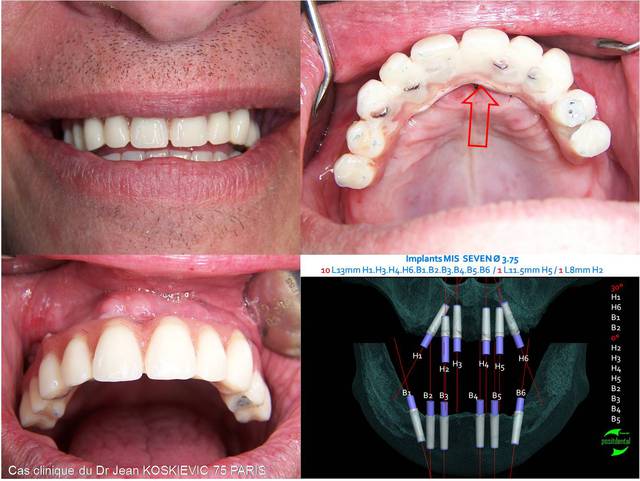

Ci-joint, le jour de la chirurgie, pose d’implants simultanée haut et bas avec lambeaux et provisoire avec barre céramisée. Les provisoires sont restés en place plus d’1 an.